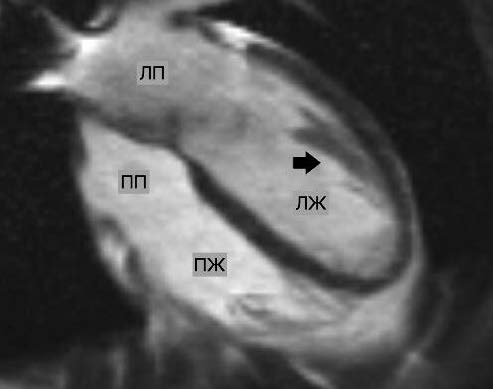

Рис. 6. МРТ сердца, короткая ось, срез на уровне средней трети ЛЖ: 1 – некомпактный слой миокарда; 2 – трабекула.

Примечание. ПЖ – правый желудочек.

Рис. 7. МРТ сердца, четырехкамерный вид. Стрелкой указаны трабекулы.

Примечание. ЛП – левое предсердие, ПП – правое предсердие.

Заключение: МР-картина повышенной трабекулярности миокарда ЛЖ, конечно-диастолическое соотношение некомпактного и компактного слоев миокарда менее 2,3. При исследовании в кинорежиме нет изменения сократительной способности ЛЖ, что также исключает НМЛЖ, в остальном – без патологических изменений; отсутствие участков патологического накопления контрастного препарата при отсроченном сканировании исключает перенесенный инфаркт миокарда, что подтверждает СТ.

В 2005 г. S. Petersen и соавт. предложили следующий критерий НМЛЖ по данным МРТ: соотношение толщины некомпактного и компактного слоев миокарда ЛЖ более 2,3; измерение проводится по длинной оси на уровне между митральным клапаном и верхушкой ЛЖ в конце диастолы [2]. В том случае, когда толщина некомпактного слоя не соответствует принятому в настоящее время критерию, изменения в миокарде нужно расценивать как повышенную трабекулярность ЛЖ. Однако, по мнению ряда авторов, в основе повышенной трабекулярности ЛЖ могут лежать те же генетические причины, что и при развитии НМЛЖ, поэтому трансформация гипертрабекулярности в НМЛЖ может быть лишь вопросом времени [3].

В нашем случае у пациентки по данным МРТ сердца диагноз НМЛЖ исключен и выявлена повышенная трабекулярность миокарда ЛЖ. Возникает вопрос: сосуществовали ли эти два состояния – гипертрабекулярность ЛЖ и СТ или они имели патогенетическую взаимосвязь?